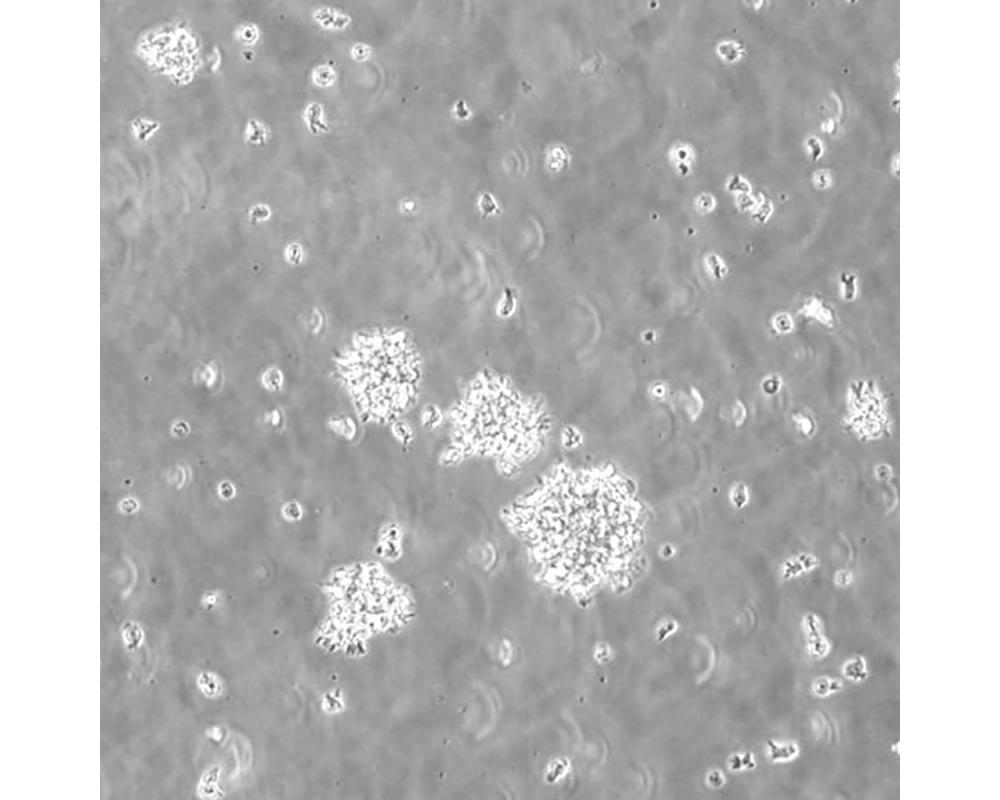

CCRF-SB

中文名稱 人急性T淋巴細胞白血病細胞

組織來源 急性T淋巴細胞白血病;男性

生長特性 懸浮